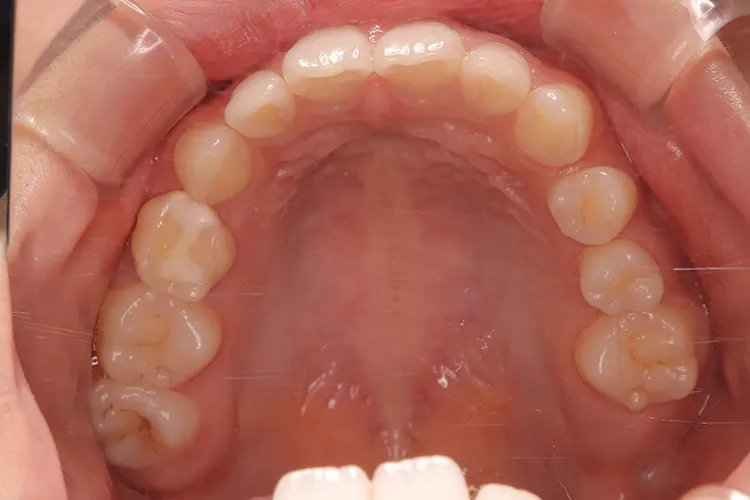

20歳の患者様の永久歯先天欠如のケースです。右上4・右下5・左下45の他、第二大臼歯も3本先天欠如していました。年齢も若いため、歯を傷める可能性の高いブリッジは選択されず、長期間安定して機能するインプラントを選択されました。このように若年者で永久歯が先天欠如しているケースにも応用できます。